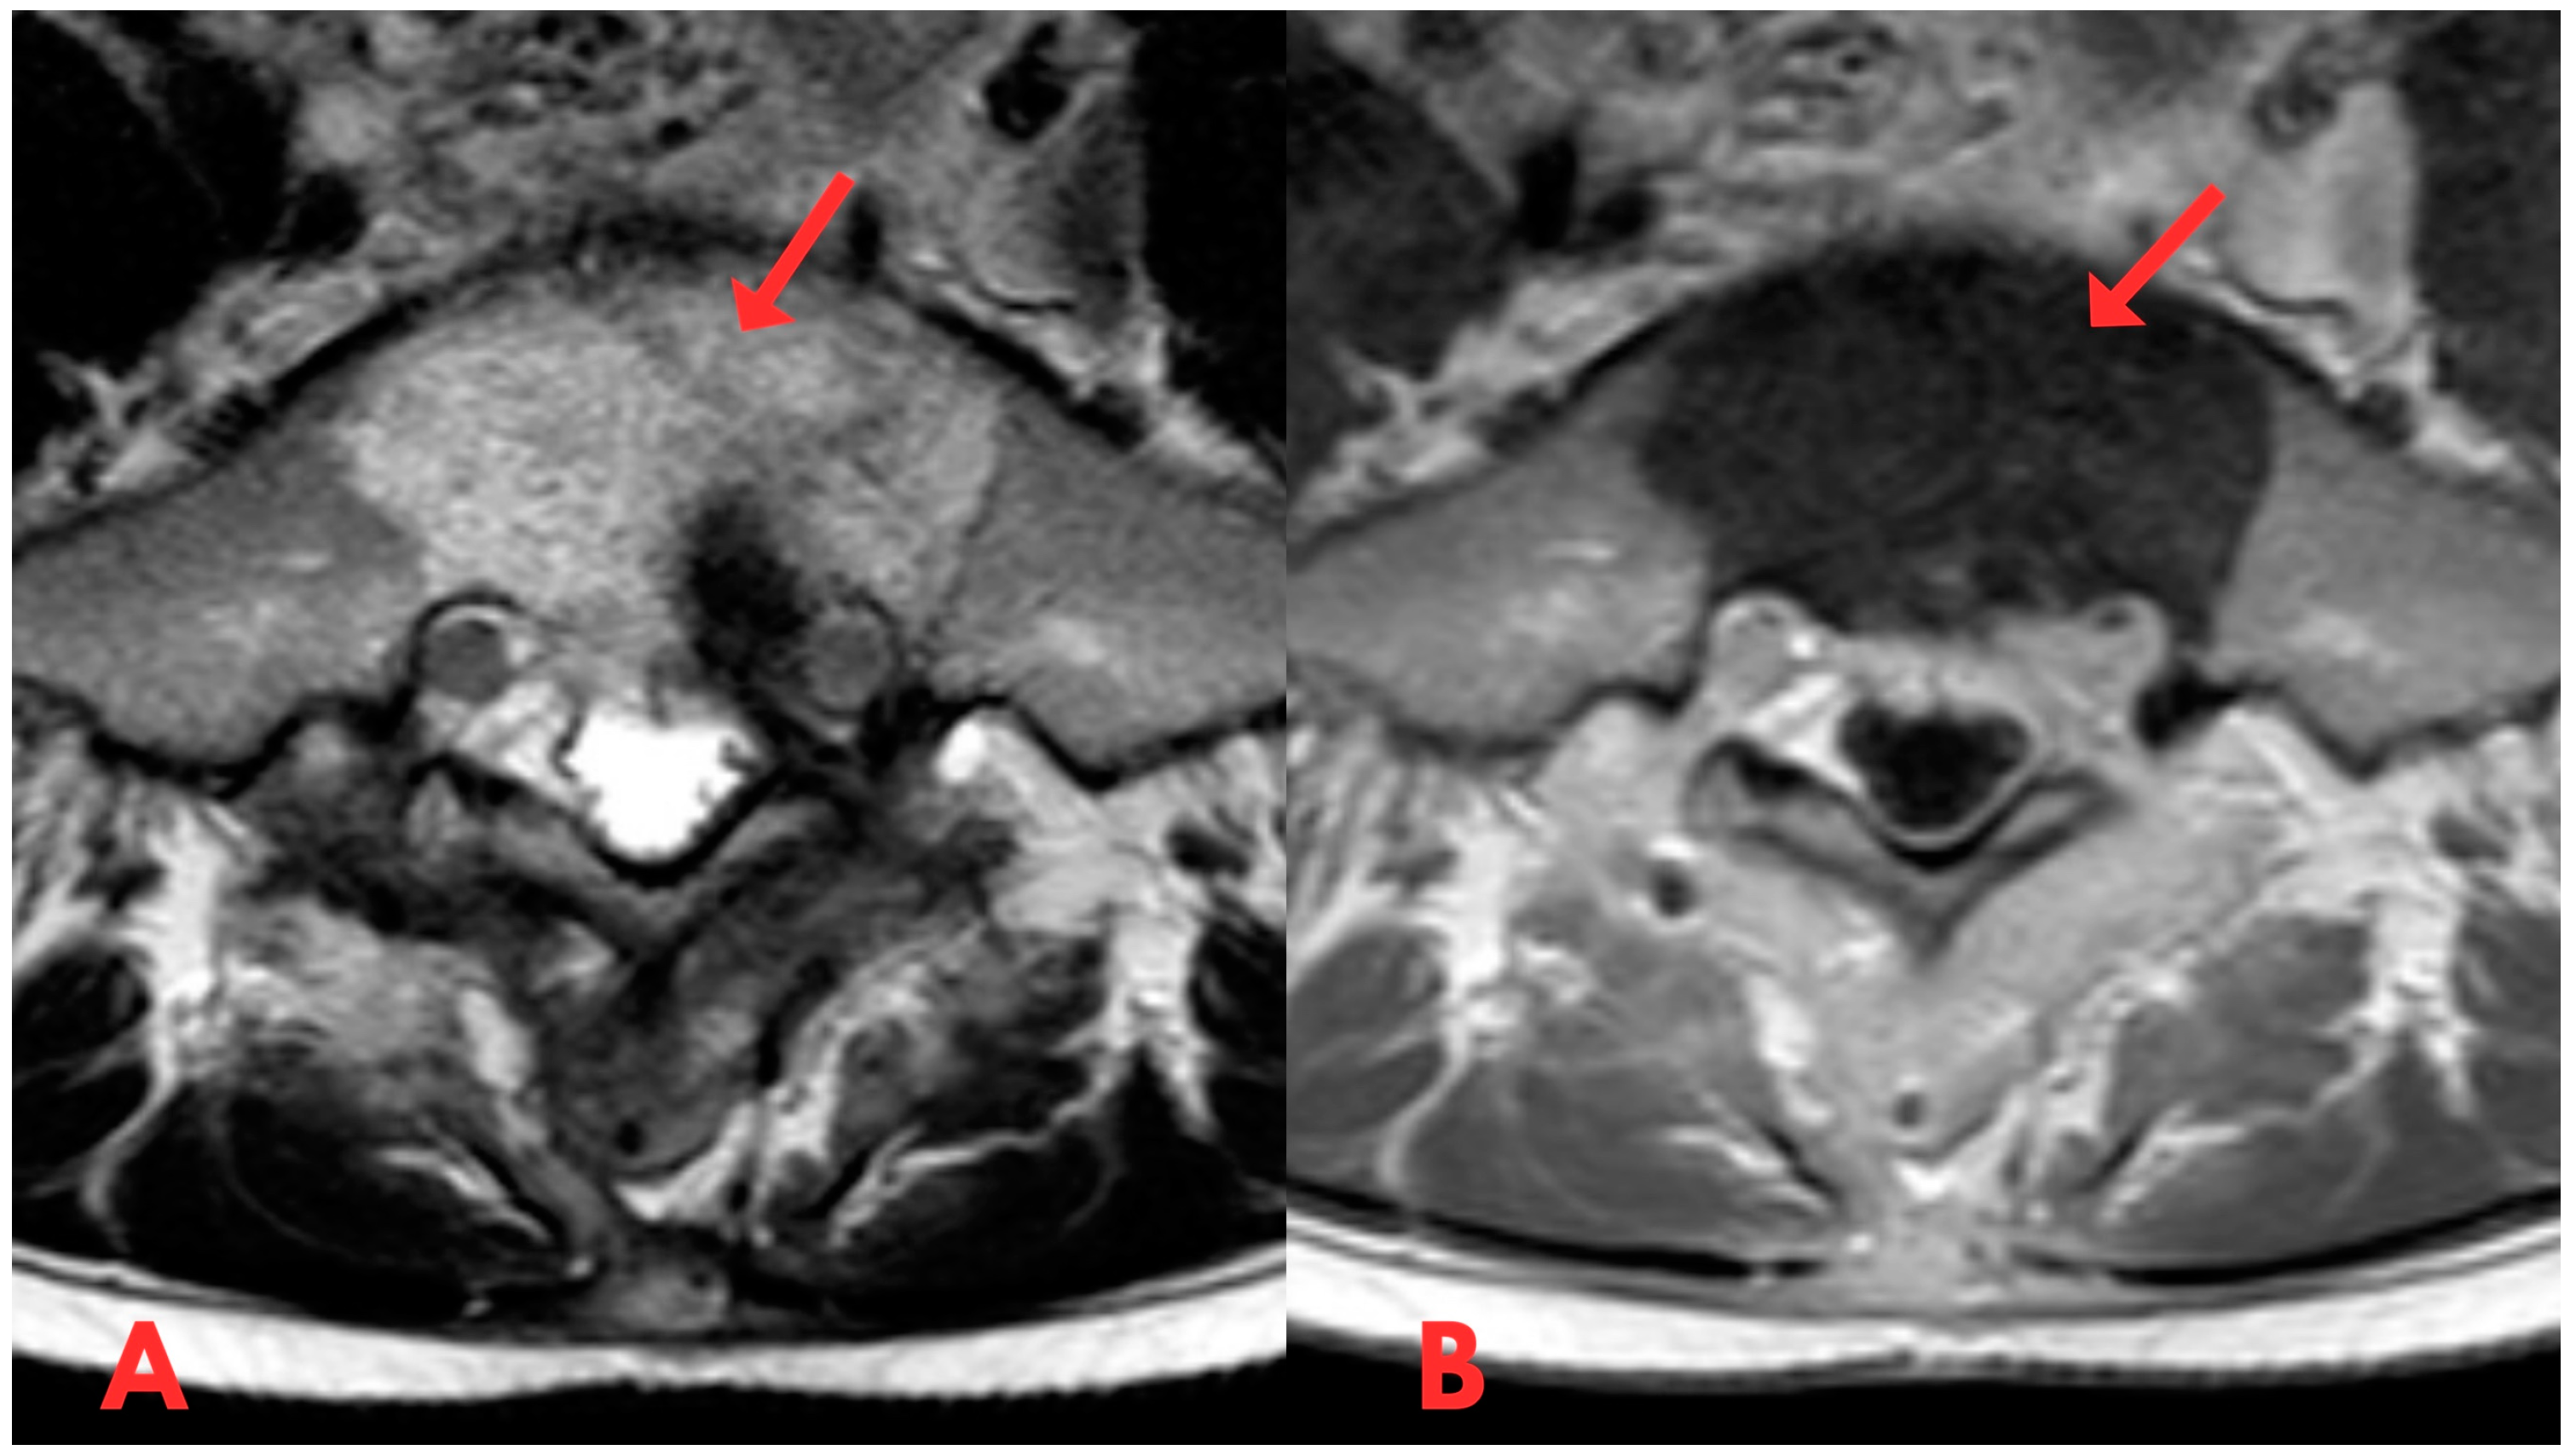

Figure 5.

(A,B) Second T1- and T2-weighted axial MRI of the lumbar spine (T2W_TSE, T1W_TSE ax) showing an S1 vertebral lesion with a hyperintense signal on T2 (A) and hypointense on T1 (B) after a biopsy. Dynamics without change in the prevertebral and spinal canal.